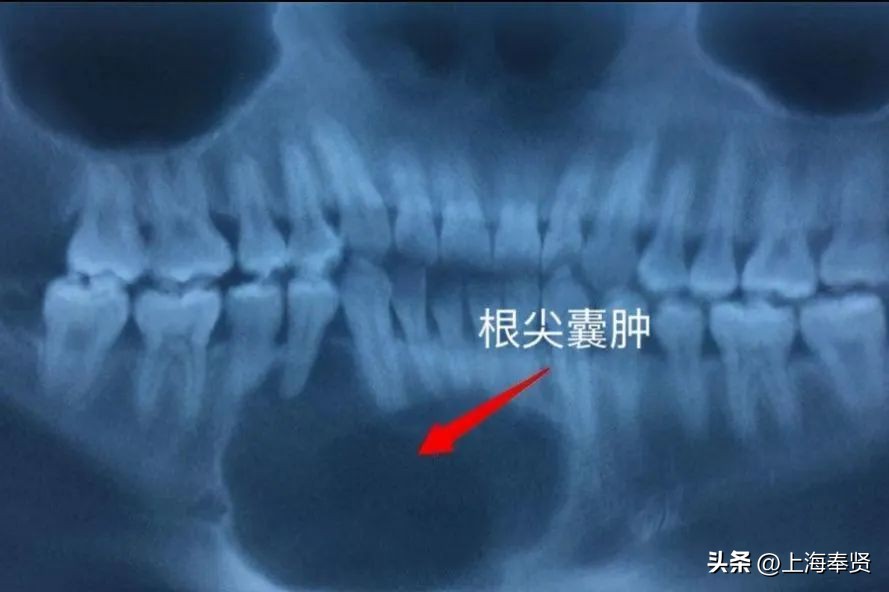

正常情况下不会受细菌侵袭,但当牙体硬组织因各种原因遭受破坏时细菌就可侵入牙髓,引起牙神经发炎而疼痛。如果牙神经发炎不做处理大概率会发生牙髓坏死,炎症得不到释放就会发展成为根尖炎、根尖脓肿、囊肿,甚至引发其他全身性疾病,所以牙神经发炎了一定要到正规的医疗机构治疗,通过抽牙神经作根管诊疗保留患牙。